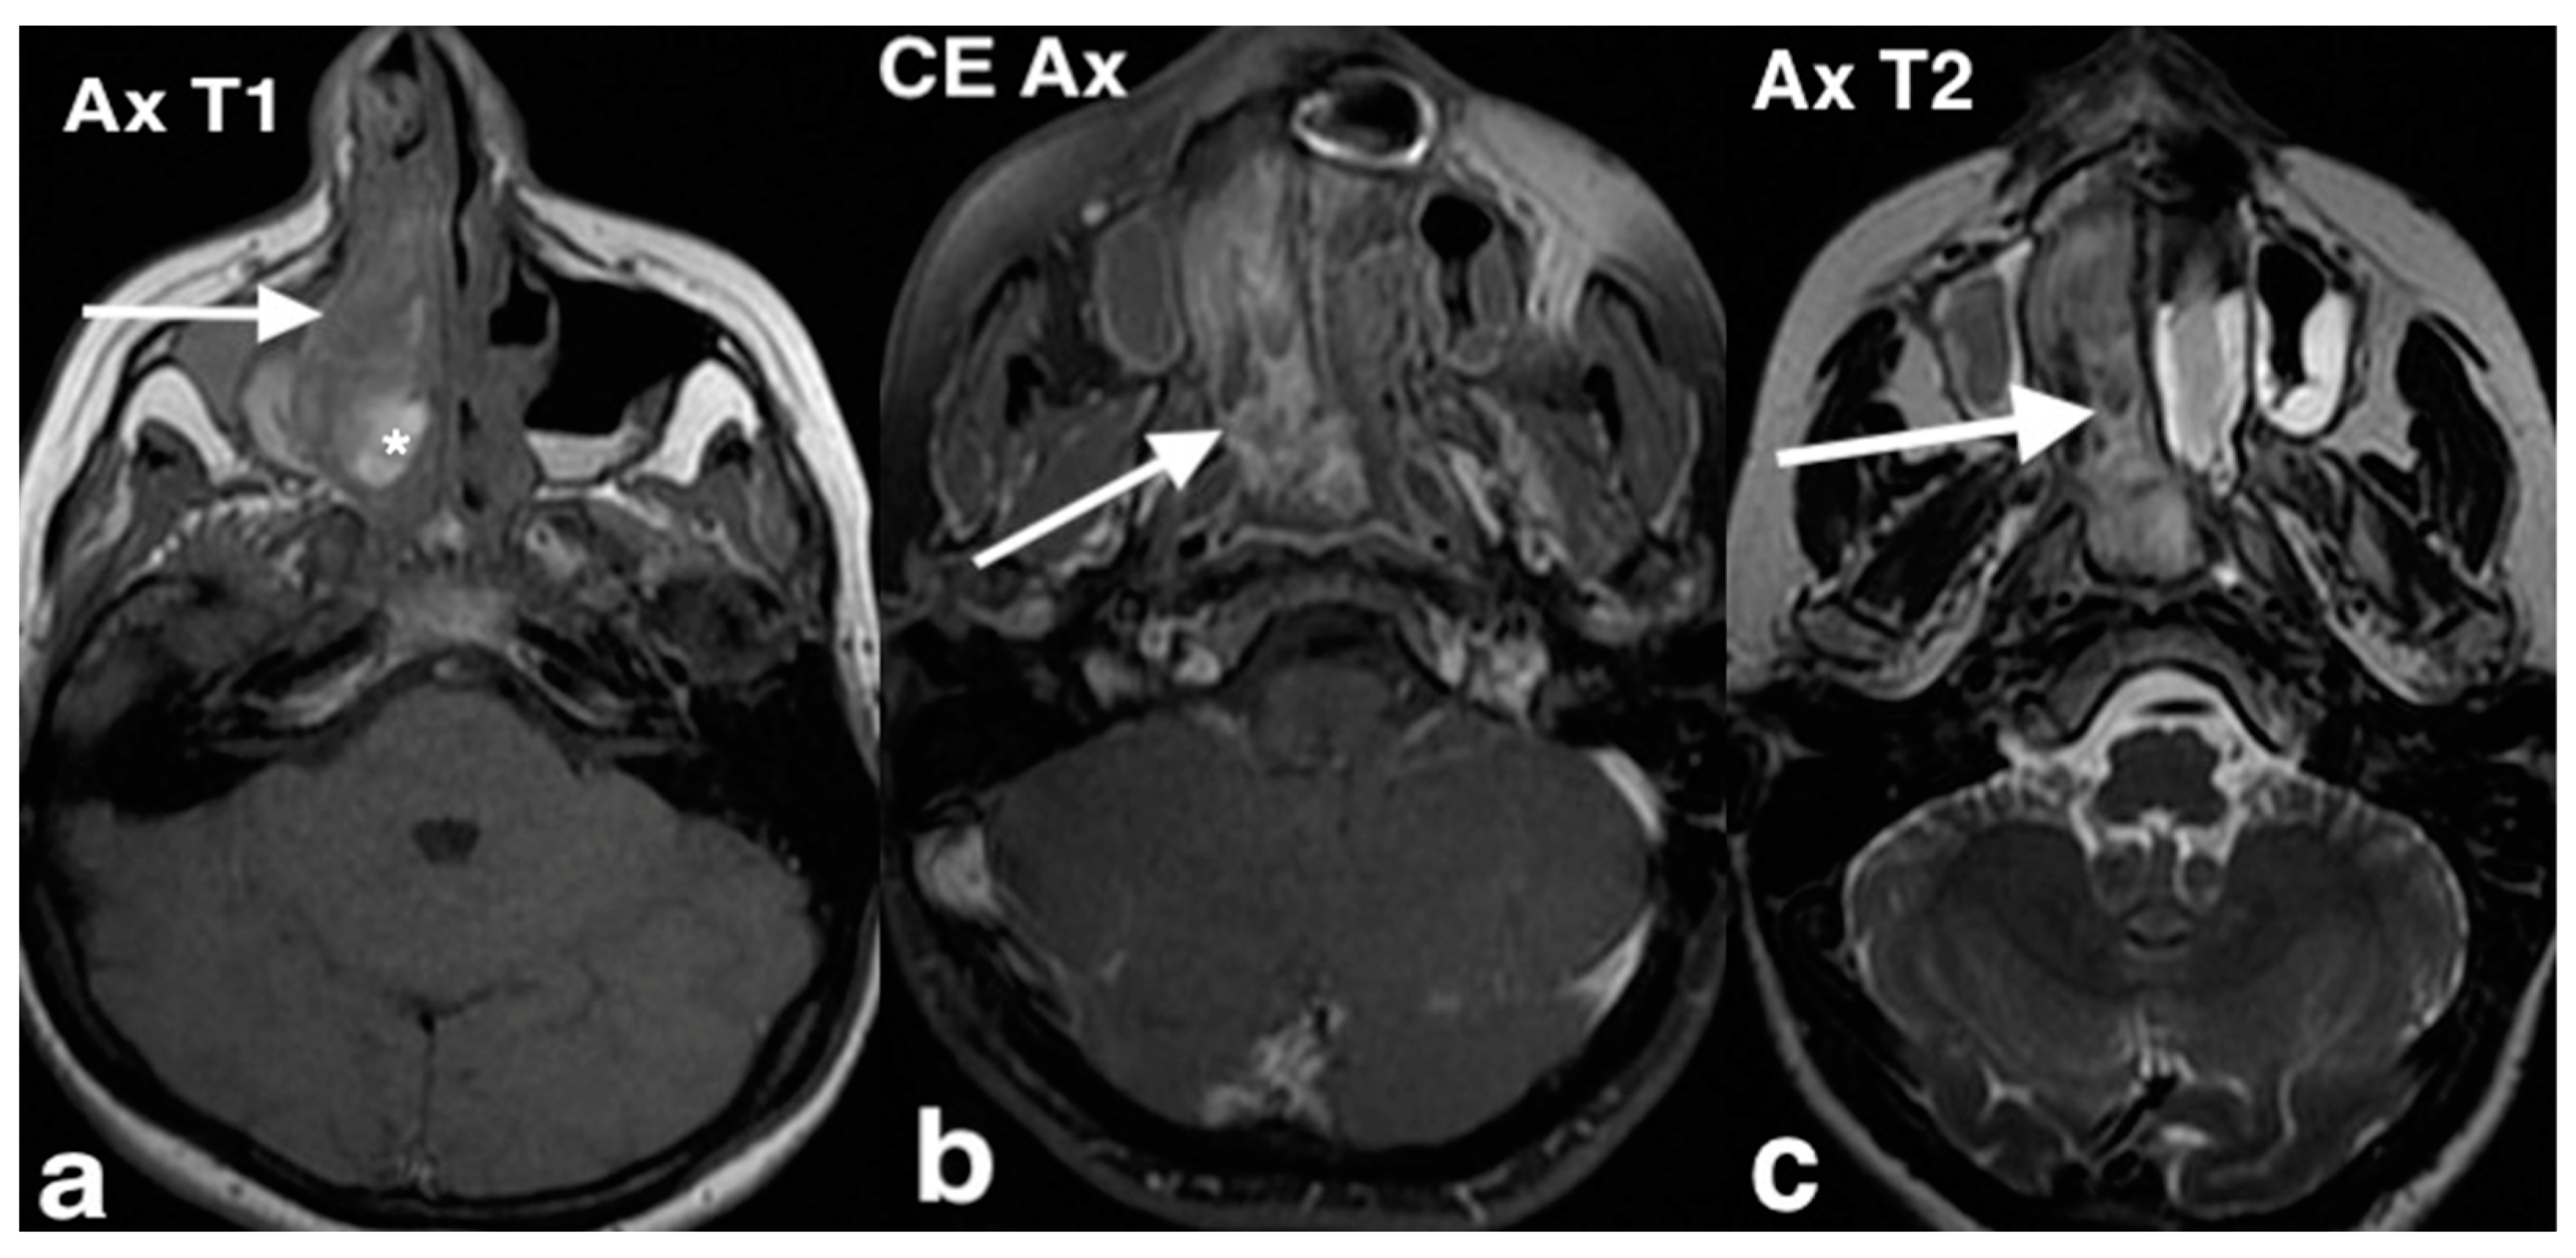

3.1.1. Septal Mucocele

3.1.2. Rinolith

3.1.3. Inverted Mesiodens